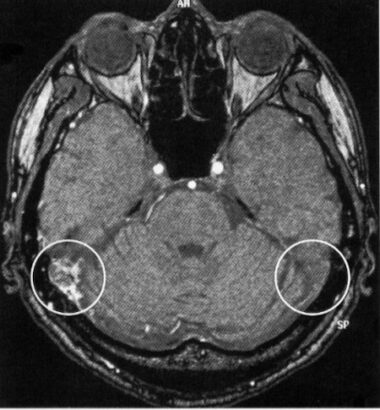

頭部MRIで発見し、脳血管造影検査で確定診断と重症度を判定します。

当然いきなり、入院して脳血管造影検査をする患者さんはいませんので、頭部MRIでの検査が重要になります。専門的な話ですが、Time of flightによるMRA検査を行い、MIP画像までしっかりと診ないと見過ごしてしまうことがあります。この病気の診断には専門性と経験が必要なため、脳神経外科専門医や放射線科専門医の読影が必須となります。

MRA検査

MRI検査の中のMRA(Magnetic Resonance Angiography:磁気共鳴血管撮影法)で、診断が可能です。しかし、診断は専門的な知識と経験が不可欠です。脳神経外科専門医によるMRI検査が必須と考えております。